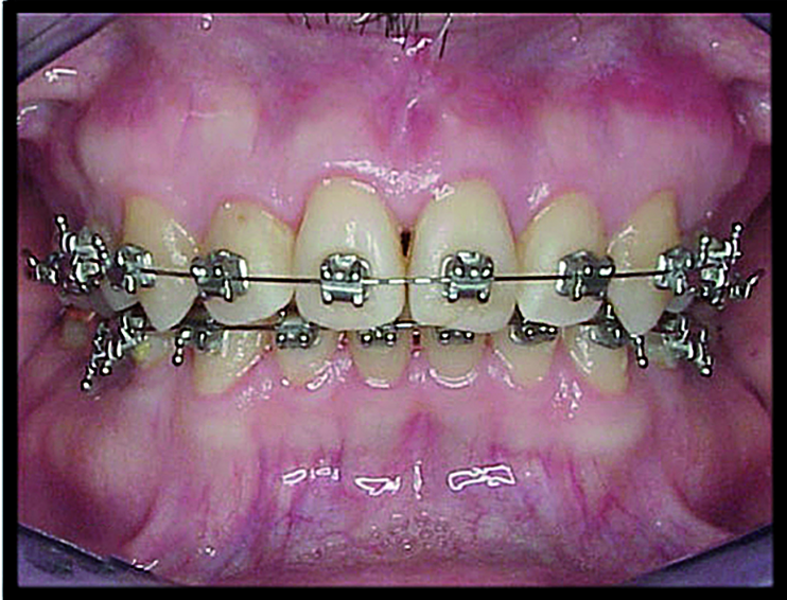

BiTurbo2 system for rapid deep overbite correction